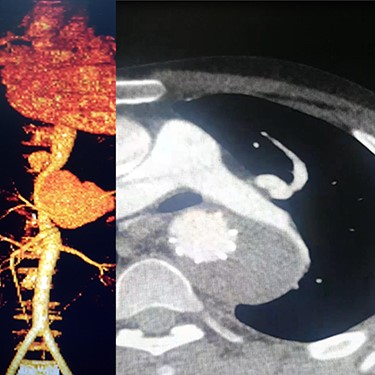

Case 1 — A 30-year-old man who was a known case of BD and was diagnosed 5 years prior to admission to our center. The patient was admitted to our hospital with progressive chest and left upper extremity pain for 4 months. Chest computed tomography (CT) scan revealed a left saccular subclavian aneurysm (Fig. 1A) with no sign of rupture or pleural effusion. After 48 hours of admission, he suffered from severe abdominal pain, hypotension and tachycardia. After resuscitation, thoracoabdominal CT angiogram (CTA) was conducted which showed an aneurysm of the thoracoabdominal aorta (Fig. 1B) and was ruptured near Celiac artery origin. Endoxan (1 gr) and Methyl prednisolon pulse (1 gr daily up to 3 days) were injected. Emergency thoracic endo vascular aortic repair (TEVAR) was performed and he became stable after the procedure. Tablet of Prednisolon 5 mg was prescribed twice daily. In follow-up angiography, the subclavian artery was ligated after the origin of the aortic arch and the aneurysm was thrombosed; however, since his arm was viable, conservative management was selected. After 1 year, he had no disabling abnormality on physical examination of his arm and no sign of endoleak was identified in the follow-up CTA.

(A) CTA of the left subclavian aneurysm (right), (B) CTA of thoraco abdomen aneurysm (left).